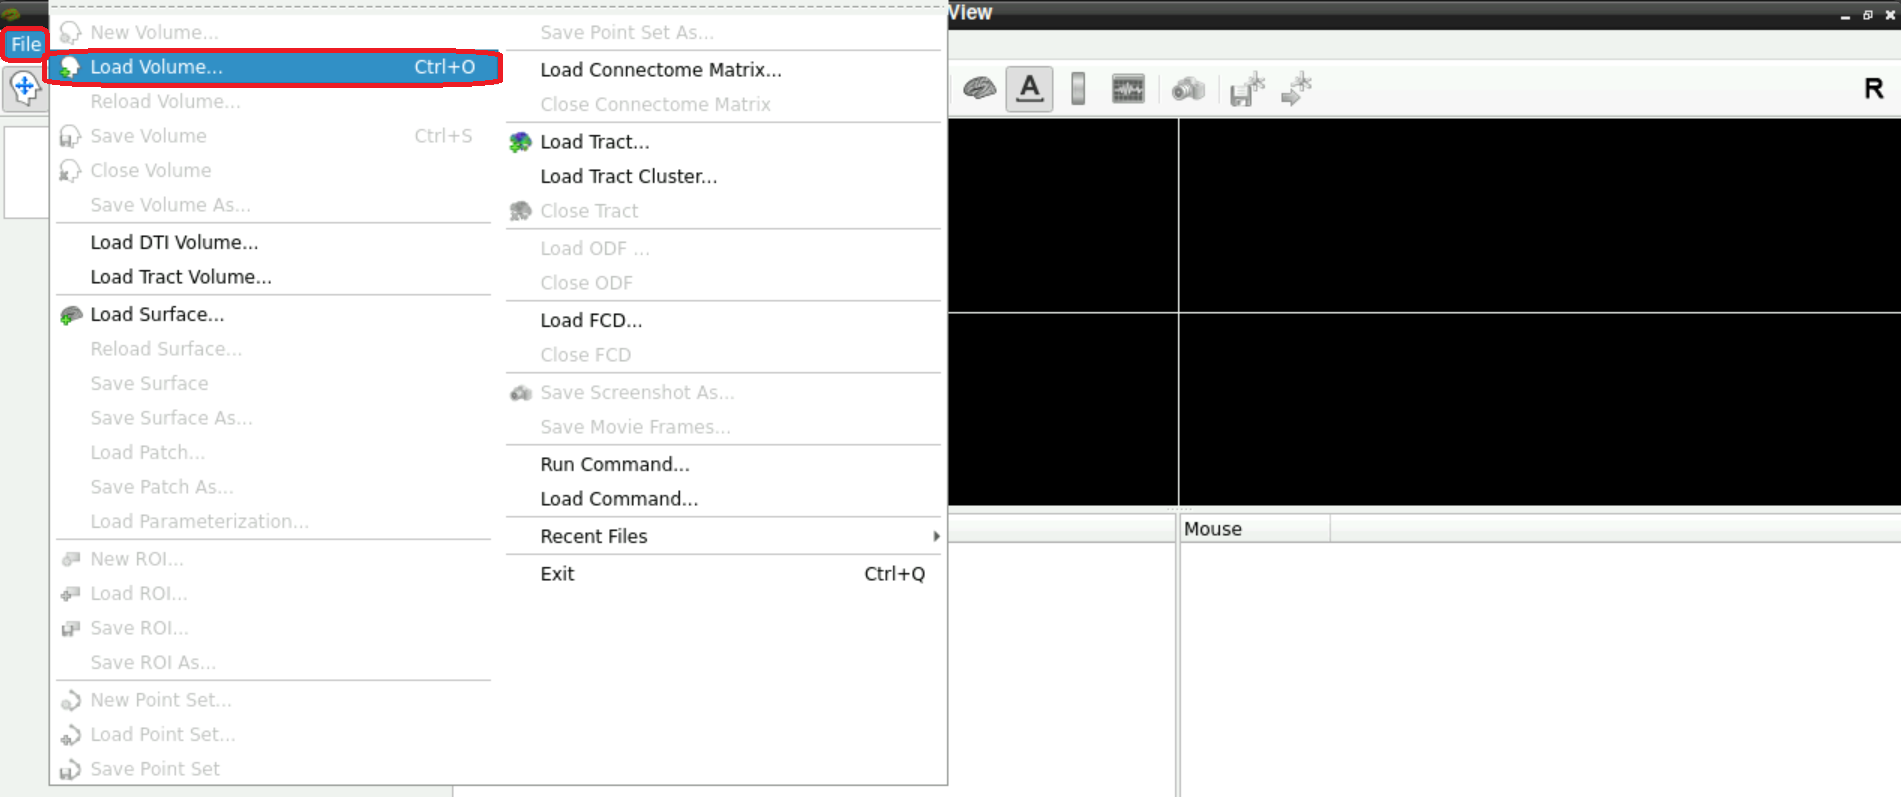

Now you have to look at a functional scan to see if there is a denoising scan at the end.

For this, select File > Load Volume (top left corner in freeview):

A new window opens, asking you to Select volume file. Either type in the path(s) to your/a functional scan manually, or start by clicking on the folder symbol

Navigate to your func directory in your BIDS, select one of the nifti files of one of the runs and press Open afterwards

Now, with the field Select volume file specified with the path(s) to the nifti file, you can click Open